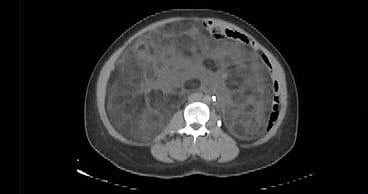

وأوضحت المدينة بأن الفريق الطبي للحالة بقيادة استشاري ورئيس وحدة جراحة أورام الجهاز العلوي والمناظير د.عبدالعزيز الربيع باشر الحالة بالفحص السريري وعمل الأشعة، تبين على إثرها وجود ورم (Sarcoma) نادر يضغط على الأعضاء الداخلية للتجويف البطني، يصل وزنه 9 كجم وبحجم ويصل إلى 45 سم كان يغطي كامل التجويف.